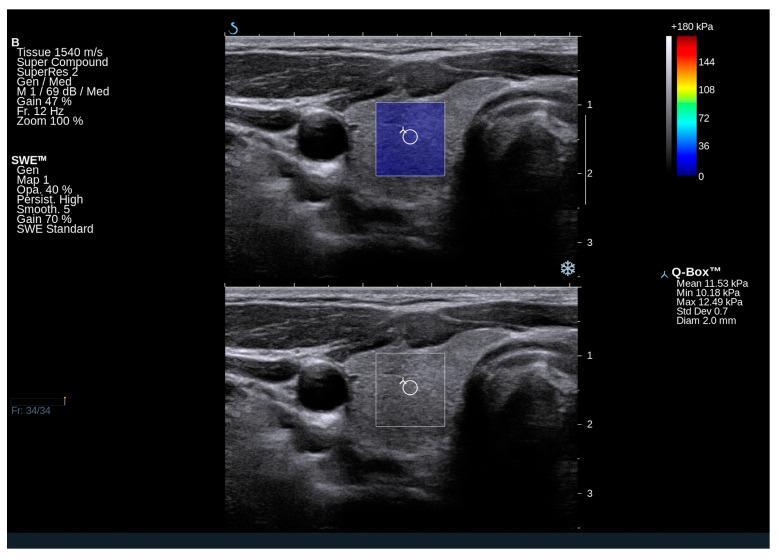

Gaucher disease (GD), the most common ultra-rare metabolic disorder, results from lipid accumulation. Systemic inflammation, cellular stress, and metabolic dysfunction may influence endocrine function, including the thyroid. This study evaluated thyroid function and morphology in 60 GD patients, alongside carbohydrate and lipid metabolism. Anthropometric, biochemical, and hormonal tests were conducted, including thyroid ultrasound and shear-wave elastography (SWE). Clinical data, bone mineral density (BMD), and body composition (BOD POD) analyses were correlated. Healthy controls, matched for age, sex, and body mass index (BMI), were included. GD patients had higher thyroid stimulating hormone (TSH) and free thyroxine (FT4) levels within normal limits. Hypothyroidism occurred in 7%, elevated anti-thyroid antibodies in 8%, and nodular goiter in 23%. Patients with nodular goiter showed lower platelet counts and higher chitotriosidase and glucosylsphingosine (lysoGb-1) levels. Patients with type 3 GD had larger thyroid volumes and greater stiffness on SWE than patients with type 1 GD. GD patients also exhibited increased metabolic risk, including central obesity and elevated glucose levels. GD patients, despite normal thyroid hormone levels, exhibit subtle alterations in thyroid function indicators. Their increased risk of central obesity and glucose metabolism disorders, alongside higher TSH and FT4 levels, underscores the need for closer monitoring and further investigation.

戈谢病(GD)是最常见的超罕见代谢紊乱疾病,由脂质蓄积引起。全身炎症、细胞应激和代谢功能障碍可能影响内分泌功能,包括甲状腺功能。本研究评估了60例GD患者的甲状腺功能和形态,以及碳水化合物和脂质代谢情况。进行了人体测量、生化和激素检测,包括甲状腺超声和剪切波弹性成像(SWE)。对临床数据、骨密度(BMD)和身体成分(BOD POD)分析进行了相关性研究。纳入了年龄、性别和体重指数(BMI)相匹配的健康对照者。GD患者的促甲状腺激素(TSH)和游离甲状腺素(FT4)水平在正常范围内较高。7%的患者发生甲状腺功能减退,8%的患者抗甲状腺抗体升高,23%的患者有结节性甲状腺肿。有结节性甲状腺肿的患者血小板计数较低,几丁质酶和葡萄糖神经酰胺(溶酶体Gb-1)水平较高。3型GD患者的甲状腺体积比1型GD患者更大,SWE检查显示硬度更高。GD患者还表现出代谢风险增加,包括中心性肥胖和血糖水平升高。GD患者尽管甲状腺激素水平正常,但甲状腺功能指标仍有细微变化。他们中心性肥胖和糖代谢紊乱的风险增加,以及较高的TSH和FT4水平,凸显了密切监测和进一步研究的必要性。